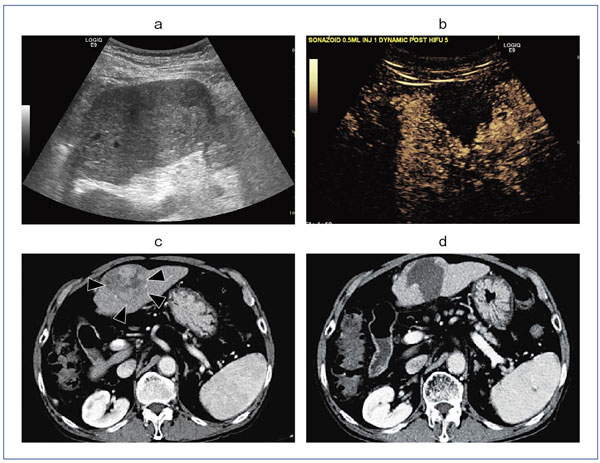

症例1(図2)は,約5cmの比較的大きな肝細胞がん(HCC)で,寝台を3mmピッチで動かしながら,腫瘍全体を焼灼した。HIFU治療は病変の大きさにより,1〜3日に分割して治療する。その日の焼灼の評価および翌日の焼灼予定範囲をより正確に確認するために,HIFU治療後,ソナゾイド造影超音波を施行する。Kupffer image(図2 b)では,焼灼領域がdefect像として描出されるほか,vascular imageでは残存血流の有無を確認することができる。治療後の評価はCTで行うことも可能だが(図2 c,d),造影超音波を用いれば,治療から効果判定までを超音波だけですませることが可能となる。

図2 症例1:約5cmの比較的大きなHCC

a:HIFU治療前の超音波画像

b:HIFU治療後のソナゾイド造影超音波画像(Kupffer image)

c:HIFU前CT画像

d:HIFU後CT画像